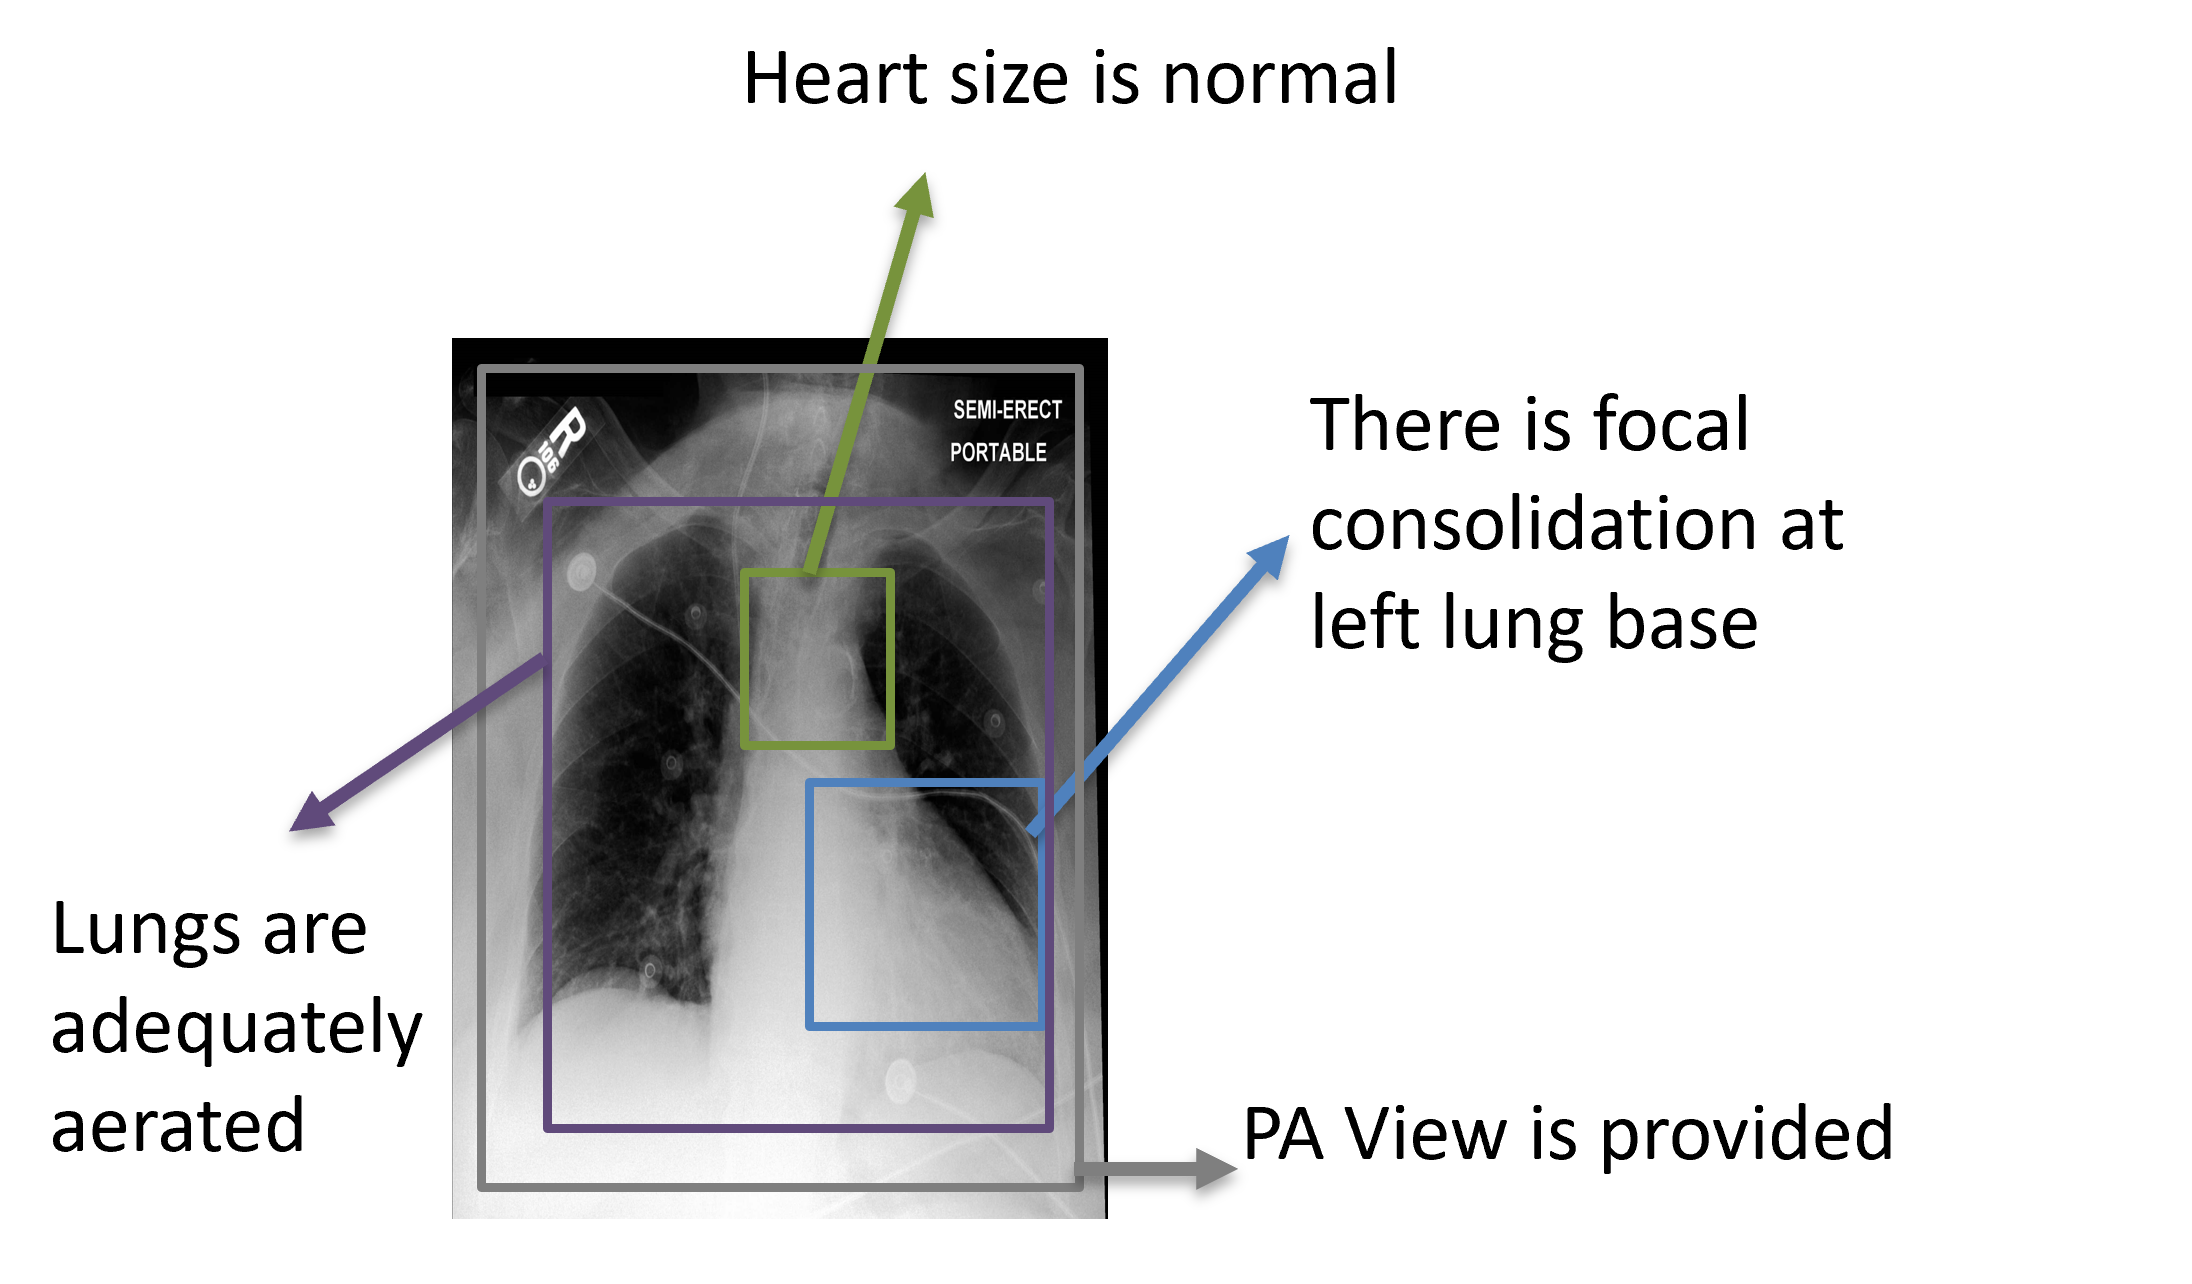

Although there are several existing methods relating to explainable face recognition [38, 25, 18, 22] they focus on indistinct visual explanations which are less interpretable than textual explanations [32]. Visual explanations can lack the nuanced detail and context often provided in textual explanations and may be subject to misinterpretation [32]. While prior works dealt with explaining the chest x-ray diagnosis made by deep learning models, none have explored using fine-grained, and atomic characteristic descriptors for providing radiologist-like explanations. The prior work can be mainly categorized into the explainable x-ray report generation [34] [19], or saliency maps for the x-ray images to depict the important regions for the diagnosis [31]. The ability of deep learning systems to provide human-expert-like explanations can help in regulatory compliance especially in legal proceedings, improved communication, and increased user trust and acceptance [32]. Contrary to the prior work, our approach employs precisely defined characteristic descriptors which are textual concepts to emulate the explanatory abilities of human experts in justifying facial recognition and chest x-ray diagnosis decisions, while also ensuring the faithfulness of the explanations through self-explainable architecture. An example of the explanations provided by our framework is given in figure 1.

Features in chest x-ray images are more niche and subtle, making it challenging for a generic CLIP model to capture them. We use a CLIP model pre-trained on chest X-Ray images and radiologist reports which is proposed by [6] as our image and text encoders. The CLIP image encoder and the text encoder are frozen while only the fully connected layers are trained. As we can extract the concept labels from radiologist reports, we can supervise the concepts unlike in face recognition where there was no supervision. Given a corpus of radiology reports, we extract the atomic, fine-grained characteristic descriptors from them using the Mistral 7B language model. We prompt it to disentangle the descriptors to separate sentences from the report (shown in figure 7 of supplementary material). Figure 3 (b) shows the illustration of some of the characteristic descriptors for chest x-ray used by radiologists.

Explanations: We do a quantitative evaluation of the explanations provided by our model with the labels extracted from radiologist reports. We use two metrics for our evaluation, i) METEOR ii) Rouge-L score for measuring the quality of explanations when compared against the ground truth. The evaluation results in table 3 show that we achieve a good Rouge-L score exhibiting the fidelity of our explanations. One possible reason for the METEOR score not being higher could be the difference in the ordering of concepts between the predictions and the ground truth. We do not optimize for ordering as we treat all ground truth concepts as equally important. Figure 4 shows example results of our explainable chest x-ray diagnosis system.